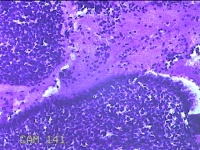

宫颈管内容物

性别

女

年龄

49岁

临床诊断

1.左卵巢子宫内膜异位症 2.盆腔子宫内膜异位症 3.异常子宫出血 4.子宫内膜息肉

一般病史

阴道出血9天。

标本名称

大体所见

纱布一块,内有灰白粉红色不规则碎组织1x0.8x0.3cm一堆。